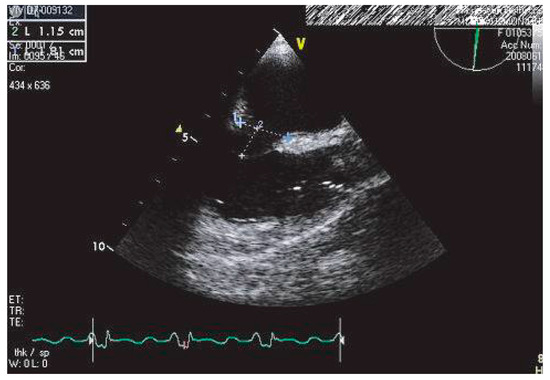

This report describes a case of involvement of inferior vena cava and the right atrium (RA) by a hepatocellular carcinoma (HCC), incidentally discovered during a transthoracic echocardiography in a patient with segmental left ventricular dysfunction,...